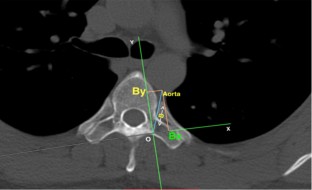

A total of 200 patients underwent CT scan of the thoracic spine in the standard supine, prone and prone position with padding. Axial CT images from T4 to T12, in all three different positions, were selected and the following parameters were measured: (a) distance B connecting left pedicle entry point to the edge of the aortic wall and (b) projections Bx and By, representing the minimum AP depth and horizontal displacement of the aortic wall relative to the left pedicle entry point O.

There was a significant difference in the distance B between the three different positions across all thoracic vertebrae levels, confirming that positioning significantly affects aorta’s relative position. Moreover, in the prone position with padding at the level of T6, the aortic wall lies at a minimum distance from the left pedicular axis and thus from the typical screw trajectory.